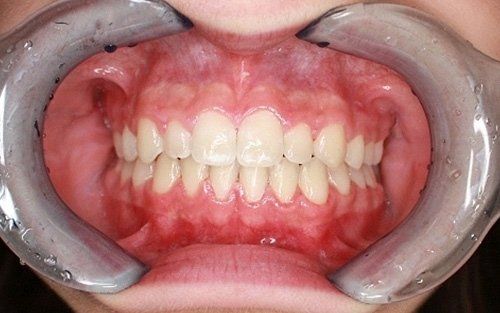

La "doppia fila" di denti: preoccupazione per i genitori

Una grande preoccupazione per i genitori è rappresentata dalla presenza contemporanea dei denti permanenti e dei denti da latte (che non cadono).Questa condizione non è affatto pericolosa per i denti permanenti, che prima o poi andranno a posizionarsi nella loro sede definitiva, dando l'ultima spinta ai dentini da latte, che cadranno definitivamente. Tranne rare accezioni, non vi è alcuna necessità di traumatizzare il bambino anticipando questo processo naturale con fastidiose estrazioni dentali.

Ecco un classico esempio di contemporaneità di denti da latte e denti permanenti. Questa situazione preoccupa sempre molto i genitori.